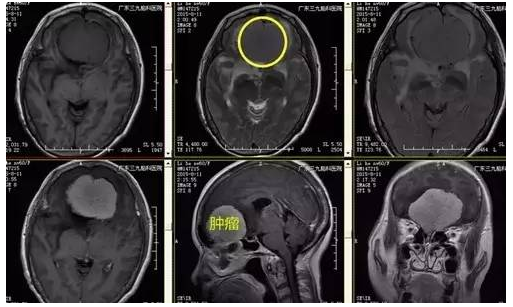

↑术前MR

李阿姨,62岁,断断续续头痛6年,当地医院治疗能有所缓解,近半年间断出现少语发作,为求进一步治疗来我院就诊,入住神经外一科,MR提示前颅窝底占位性病变,呈均匀强化,基底位于前颅窝底,病变大小约5.9*5.3cm*4.9cm,术前CTA,肿瘤血运丰富,大脑前动脉受挤压后移,考虑嗅沟脑膜瘤。

广东三九脑科医院神经外一科门诊专家刘振业主任介绍:嗅沟脑膜瘤占颅内脑膜瘤的4.45%,多见于30-50岁中年,女性多于男性,多呈球形生长,可为单侧或双侧生长,临床症状主要有嗅觉障碍、颅内压增高、视力减退、癫痫和精神异常等,嗅觉障碍也常被误诊为“鼻窦炎”而延误诊断。本例患者为老年女性,病变呈双侧生长,形状形似“桃子”,有颅内压增高所致头痛症状及精神异常。